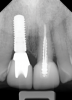

Fig 3. In a separate case, radiograph of a decayed endodontically treated tooth is shown. The decision was made to extract it before further damage to adjacent teeth and/or loss of bone could occur.

Figure 3

Fig 4. Radiograph of the implant to replace the tooth in Fig 3 (implant placed by David Levine, DDS).

Figure 4

Fig 12. In a separate case, radiograph of implant No. 8 is shown. Previous endodontically treated tooth had fractured and the decision was made within a few months to extract and replace it with an implant. Bone was preserved to optimize the implant site.

Figure 12

Fig 13. Successful final restoration of implant No. 8. Had the clinician waited too long to extract the failing endodontically treated tooth No. 8, the result may have been compromised, especially if the patient had a high smile line.

Figure 13